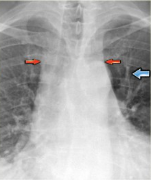

Stage III-Alveolar edema.

Prominent vena azygos dan peningkatan pelebaran pedikel

vaskuler (anak panah merah); konsolidasi perihilar dan

bronkogram-udara (anak panah kuning); cairan pleura

(anak panah biru); bayangan

jantung membesar (kepala panah merah)